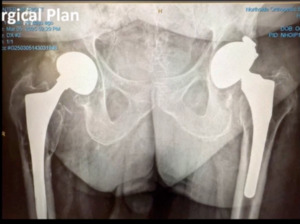

Also, I definitely like to avoid multiple implant representatives and companies, and in the OR, I like to stick with one. One of the problems I see is that there’s just so many people in the operating room. I have to “get 'em out of the way.” Actually, I can even operate on people. That’s important. That would be number six. Just to show you a case example this was a male patient came in with bilateral hip pain. (Figure 5)

His hips were done quite a while ago and recently, he had a coronary artery bypass. He’s got melanoma venous insufficiency. Just very exciting history. He’s pretty much a B bordering, not a C patient, but a definitely a B patient. We aspirated his right hip. It was negative, but the left hip unfortunately was positive on aspiration. He came back polymicrobial on next generation sequencing. But the only bug we came up with on culture was a corynebacterium. He had asymmetrical poly wear. We also did a metal ion workup through blood testing and he had really high metal ion levels. I was really concerned that he had worn through in an area and had metal ion activity. To look at it face value you’re prone to say, “okay, we can do that.” But things don’t always work out well.

But nevertheless I applied all these steps. All these pearls to get us to a point where we operated. The right hip was fine at least for right now. The left hip that’s infected. I suggested that we do a two-stage revision. The patient endorsed that. Why did we do it? The following is the report we received. (Figure 6)